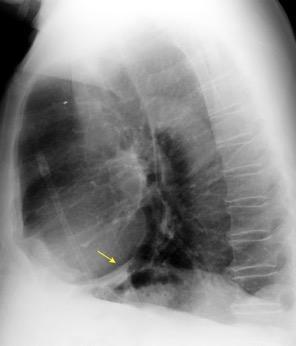

Tromboembolismo pulmonar Diafragma elevado 20%

Atelectasia crónica de LLI en paciente con enfermedad neuromuscular.

Consolidación por Infarto pulmonar. (TEP)

Visible en 2/3 posteriores

El corazón borra el1/3 anterior